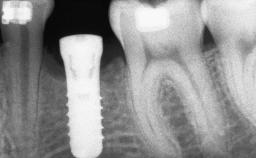

# of Implants 14

Type of Implants Two-Piece

Bone Volume Deficient vertically or deficient vertically AND horizontally